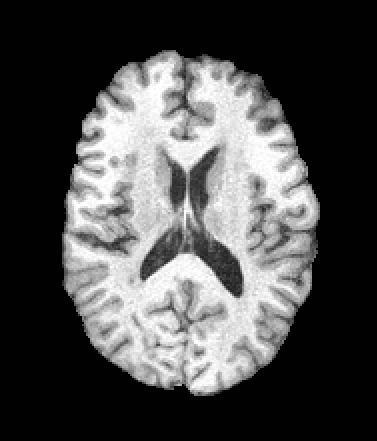

A trained MetaVoxel model can be unconditionally sampled by drawing Gaussian or categorical noise for each variable at timestep , and iteratively apply the denoising network until reaching . Unlike conventional diffusion models that focus solely on image generation, MetaVoxel can generate coherent synthetic patient profiles from the joint distribution , as shown in Figure 2.

| Age: 64.0 | Age: 53.8 | Age: 70.9 | Age: 76.9 |

| Sex: Male | Sex: Female | Sex: Female | Sex: Male |

![]() |

| Age: 80.9 | Age: 77.7 | Age: 73.2 | Age: 84.6 |

| Sex: Male | Sex: Female | Sex: Female | Sex: Female |